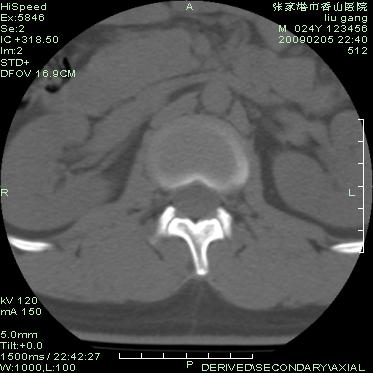

以下是引用随光逐影在2009-3-11 14:43:00的发言:[br]平片:l3、4、5及s1前上缘见类似“切角征”。[br]ct扫描:腰椎多个节段椎间盘向椎体内(椎体前部)突出。